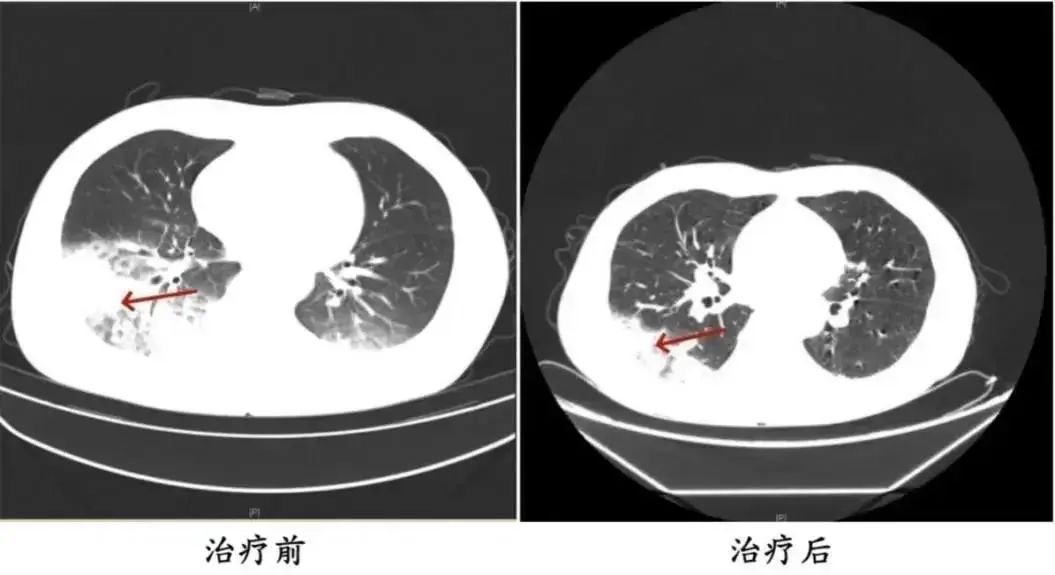

△周先生治疗前后的肺部CT影像与周先生同一时间入院的